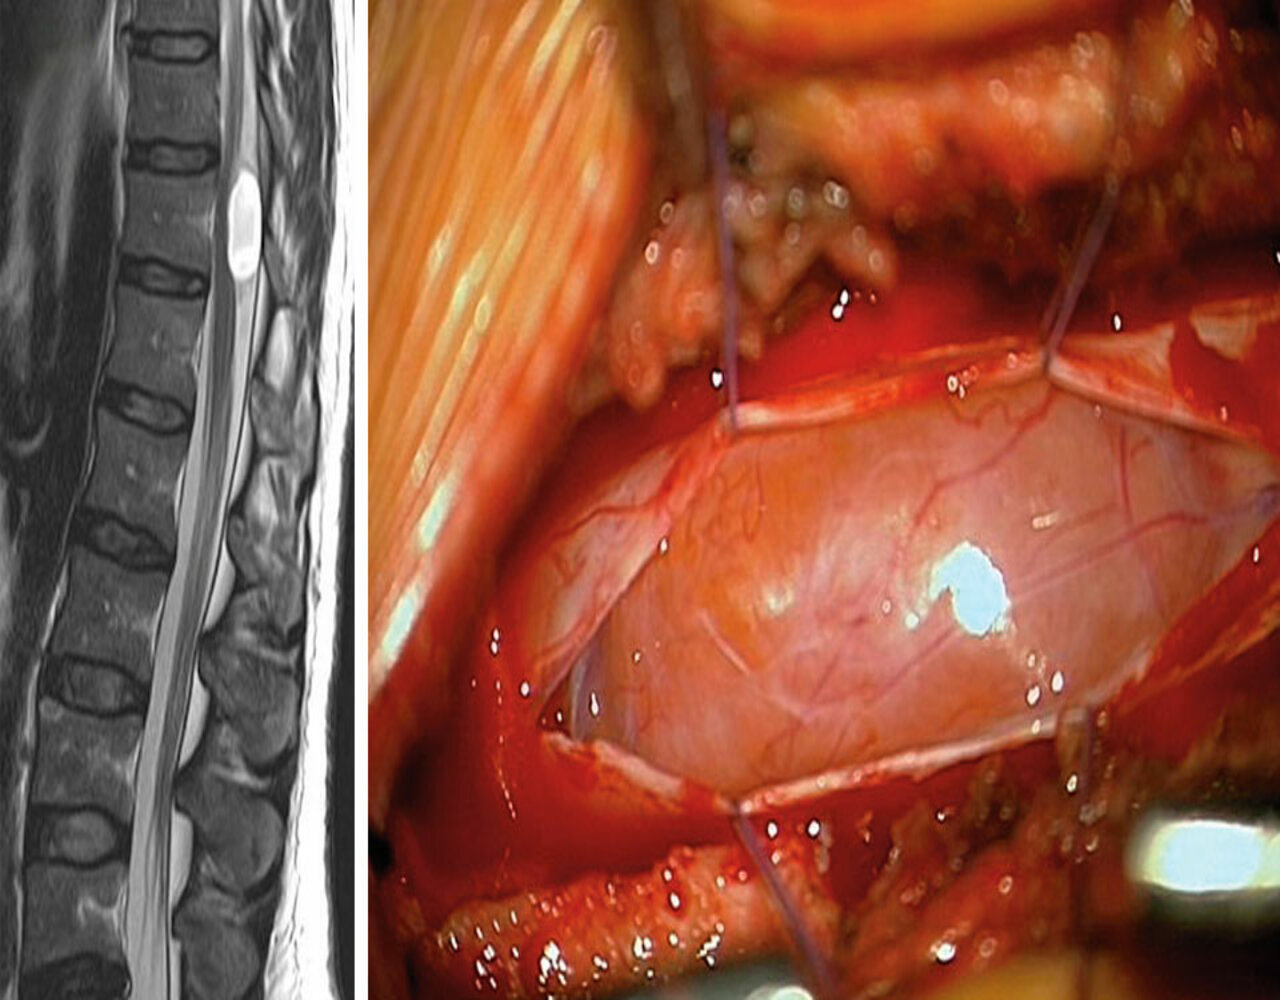

Fall 1

Ein 37-jähriger Soldat konsultiert den Truppenarzt wegen seit einem Jahr bestehender Leistenschmerzen. Die radiologische Diagnostik förderte eine Raumforderung auf Höhe BWK 11 zutage, die auch vom mitbeurteilenden Neurochirurgen als unkomplizierte Zyste ohne Zusammenhang mit den Beschwerden gewertet wurde. Obwohl man in einer erneuten MRT-Untersuchung zwei Jahre später eine Größenzunahme der Läsion feststellte, blieben die Ärzte bei dieser Einschätzung. Dies änderte sich erst, nachdem der Patient vom Truppenarzt ins Bundeswehrkrankenhaus geschickt wurde, um eine Zweitmeinung einzuholen.

„Größenprogredienz, randständige Kontrastmittelaufnahme sowie eine zwischenzeitlich aufgetretene Gang­unsicherheit schienen nicht für eine unkomplizierte Zyste, sondern vielmehr für einen rückenmarkkomprimierenden zystischen Tumor zu sprechen“, schreiben Dr. Schulz und seine Kollegen. Intra­operativ stellte sich der Befund als Schwannom heraus, das vollständig entfernt werden konnte. Schmerz und Ganganomalie wurden durch den Eingriff beseitigt.